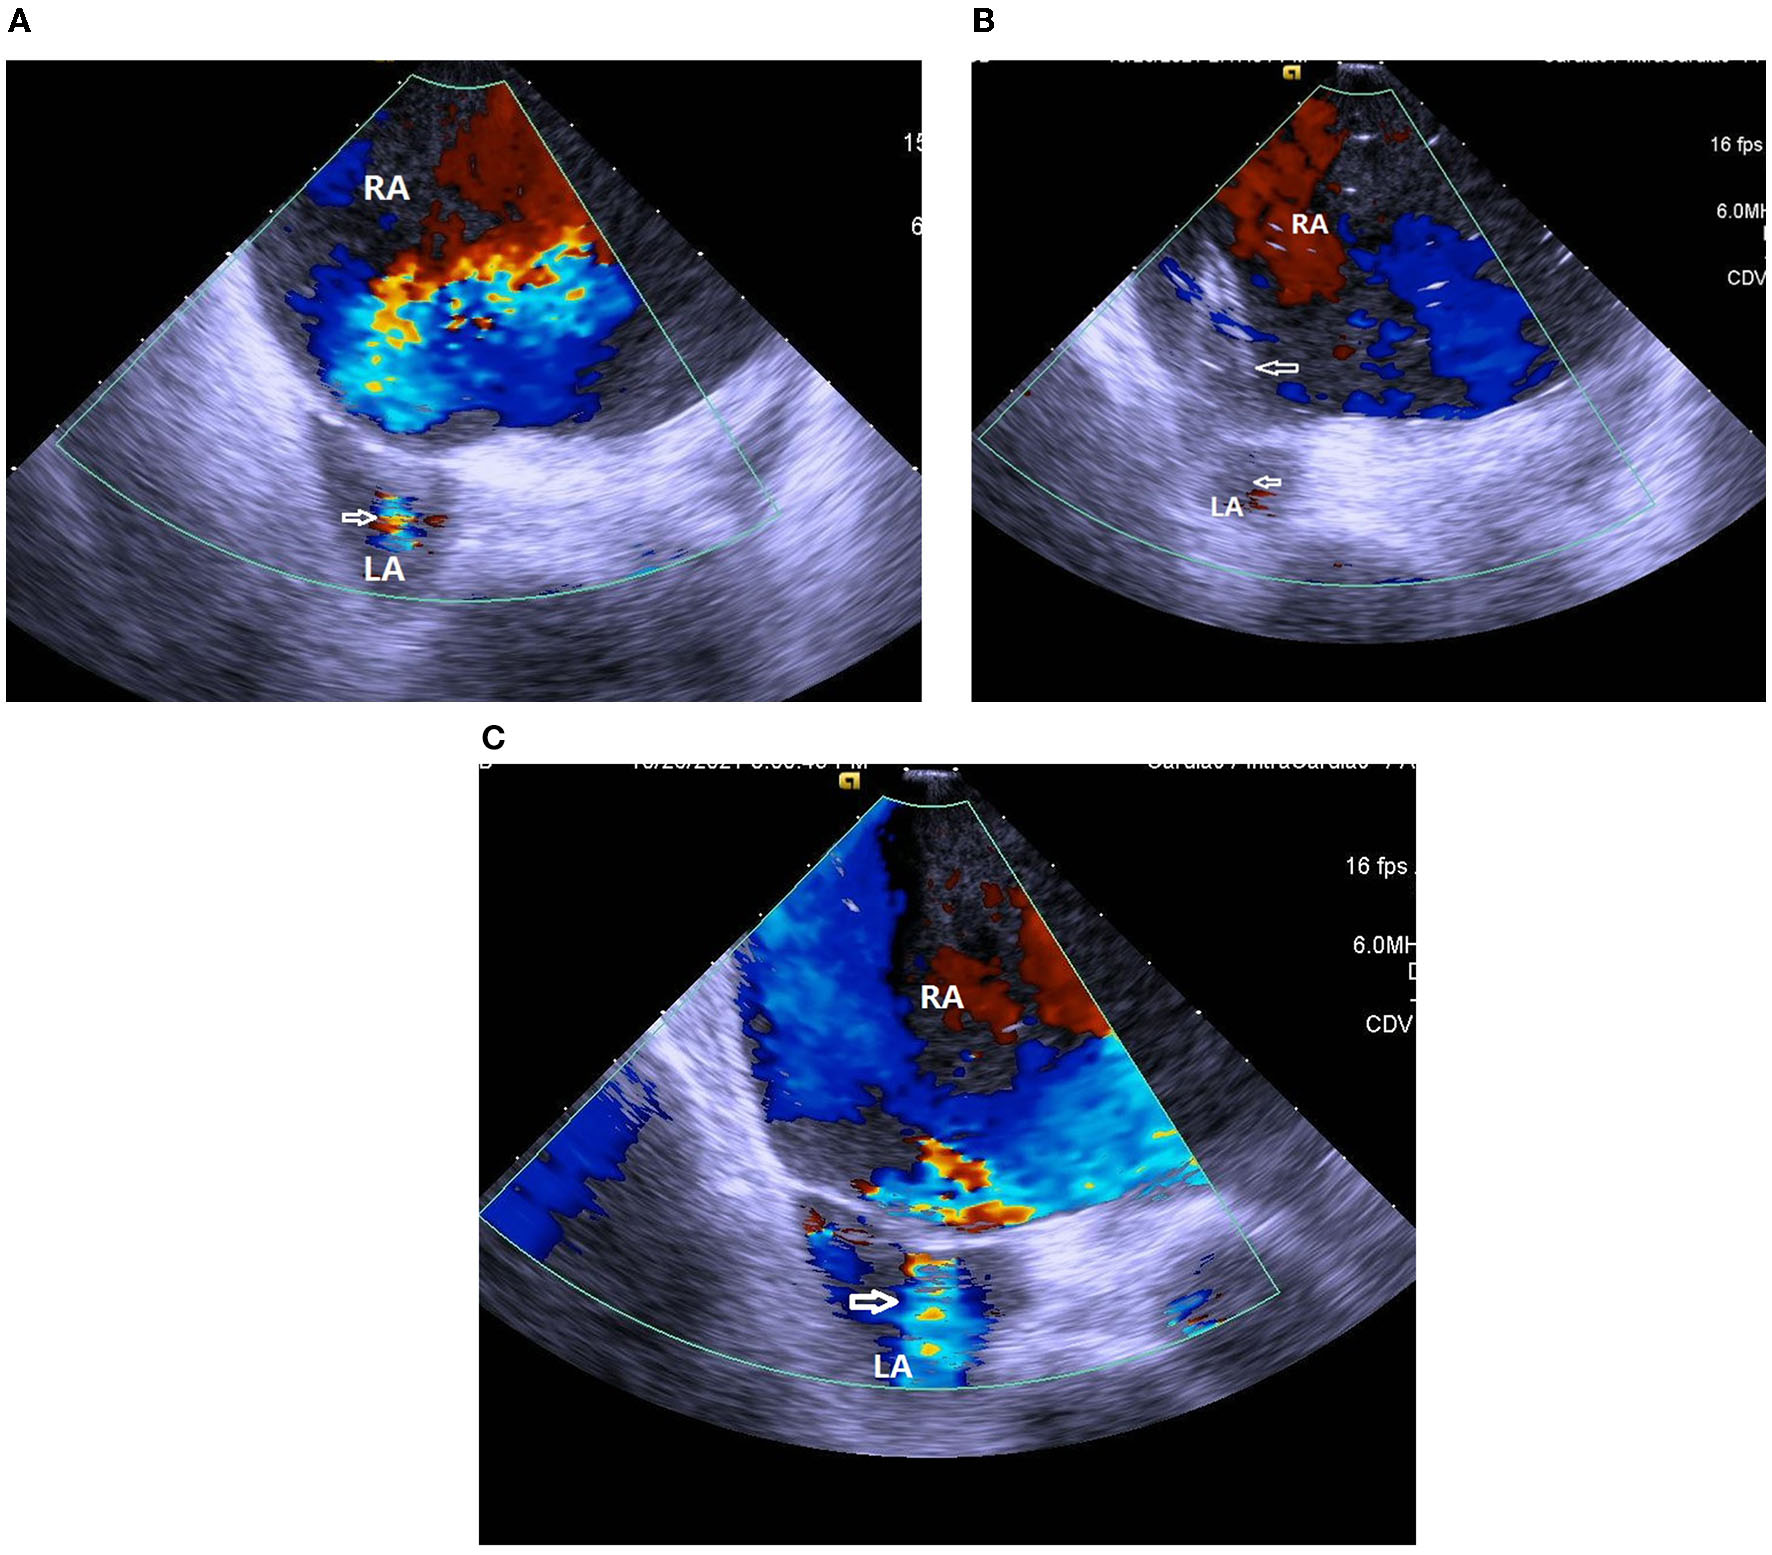

A 37-year-old woman with IPAH had received maximal target medications including oral phosphodiesterase type-5 inhibitor, endothelin receptor antagonist, and subcutaneous PA (treprostinil) injection. Other than IPAH, she had no remarkable past medical history. In April 2020, she developed worsening right heart failure with peripheral edema, oliguria, and hypotension (1st index admission). Upon admission, her systolic blood pressure was 92/76 mmHg, pulse rate was 107 beats/min, pulse oximetry was 91% in room air, and respiratory rate 20/min. Physical examinations revealed a jugular venous giant V wave with estimated central venous pressure ≥ 20 cmH2O, a grade II pansystolic murmur, and a palpable heave at the left lower sternal border. Laboratory data showed anemia with hemoglobin 7.8 g/dL, hypokalemia 3.0 mEq/L, and elevated NT-pro BNP of 4,138 g/dL. Trans-thoracic echocardiogram revealed a marked dilated RA and right ventricle (RV), in addition to a small and compressed left atrium (LA) and left ventricle (LV) (Figure 1A). She had a transition of subcutaneous to IV PA injection via a peripherally inserted central catheter (PICC) and was registered for a lung transplantation waiting list. On the 7th day of admission, we performed standard right and left heart catheterization. The baseline mean RA pressure was 14 mmHg, aortic oximetry was 96% under oxygen supply at 3 L/min through a nasal cannula, systemic CO was 2.9 L/min, and systemic OD was 291 cc/min (Table 1). An intracardiac echocardiogram (ICE) catheter (AcuNac catheter, Siemens, Mountain View, CA, USA) was introduced via the left femoral vein into RA, and the image was displayed on an ACUSON SC 2000 System (Siemens, Mountain View, CA, USA). Using real-time ICE guidance, the inter-atrial septum and fossa ovalis were clearly visualized. We used a transseptal Brockenbrough needle and a Mullins sheath (Medtronic, Minneapolis, MN, USA) to probe the inter-atrial septum before entering the LA cavity under ICE guidance (Figure 1B). The atrial septum was subsequently dilated with a 5 mm × 8 cm and 6 mm × 8 cm Mustang balloon (Boston Scientific, MA, USA) (Figure 1C). After BAS, systemic CO was increased to 3.5 L/min and OD to 318 mL/min, while the systemic arterial oxygen saturation was dropped down to 87% (under nasal cannula 3 L/min oxygen supply) (Table 1). However, we observed no immediate fall of the RA pressure (Table 1). Transthoracic echocardiogram confirmed the establishment of an inter-atrial shunting from right to left (Figure 1D). After BAS in conjunction with continuous IV PA infusion, her heart failure symptoms were alleviated to function II. Her symptoms remained stable thereafter. One and a half years later, she was re-admitted for changing the PICC and to receive cardiac catheterization again as well. ICE confirmed the presence of an interatrial shunt created by previous BAS (Figure 2A). The second baseline hemodynamic data revealed mean RA pressure of 5 mmHg, LA pressure of 2 mmHg, and systemic CO of 3.3 L/min and OD of 403 mL/min. The findings were in support of the sustained hemodynamic improvements (Table 1). The second course of BAS was done with an 8 mm balloon (Figure 2B). ICE showed increased shunting from right to left after the second BAS (Figure 2C). Post second BAS catheterization measurements revealed mean RA pressure of 3 mmHg, LA pressure of 3 mmHg, systemic CO 3.4 L/min, and OD of 420 cc/min (Table 1). She was discharged with stable functional II symptoms.

Figure 2

(A) ICE confirmed the presence of interatrial shunting (white arrow) created by previous balloon atrial septostomy. RA, right atrium; LA, left atrium. (B) ICE showed inflation of an 8 mm balloon (white arrows) at the second session of balloon atrial septostomy. RA, right atrium; LA, left atrium. (C) ICE showed an increase of right to left shunting (white arrow) after second session of balloon atrial septostomy. RA, right atrium; LA, left atrium.

For this patient, we added procedural refinements to improve the safety and efficacy of BAS. First, we followed the existing guidelines and literature to perform a graded septum dilatation (1, 6, 10). Our patient received 5, 6 mm balloon dilatation in the first BAS session and 7, 8 mm balloon dilatation in the second BAS session at an inter-session interval of 1.5 years. Second, the current guidelines and literature suggest avoiding very high-risk scenarios, such as mean RA pressure > 20 mmHg or room air pulse oximetry <85% (3, 6, 10). The patient was treated in line with the current recommendations. Third, we used ICE to guide the interatrial septum puncture, providing an instant clear view of the septum tenting sign (Figure 1B) and sparing the need for transesophageal echocardiogram and tracheal intubation (4, 5).